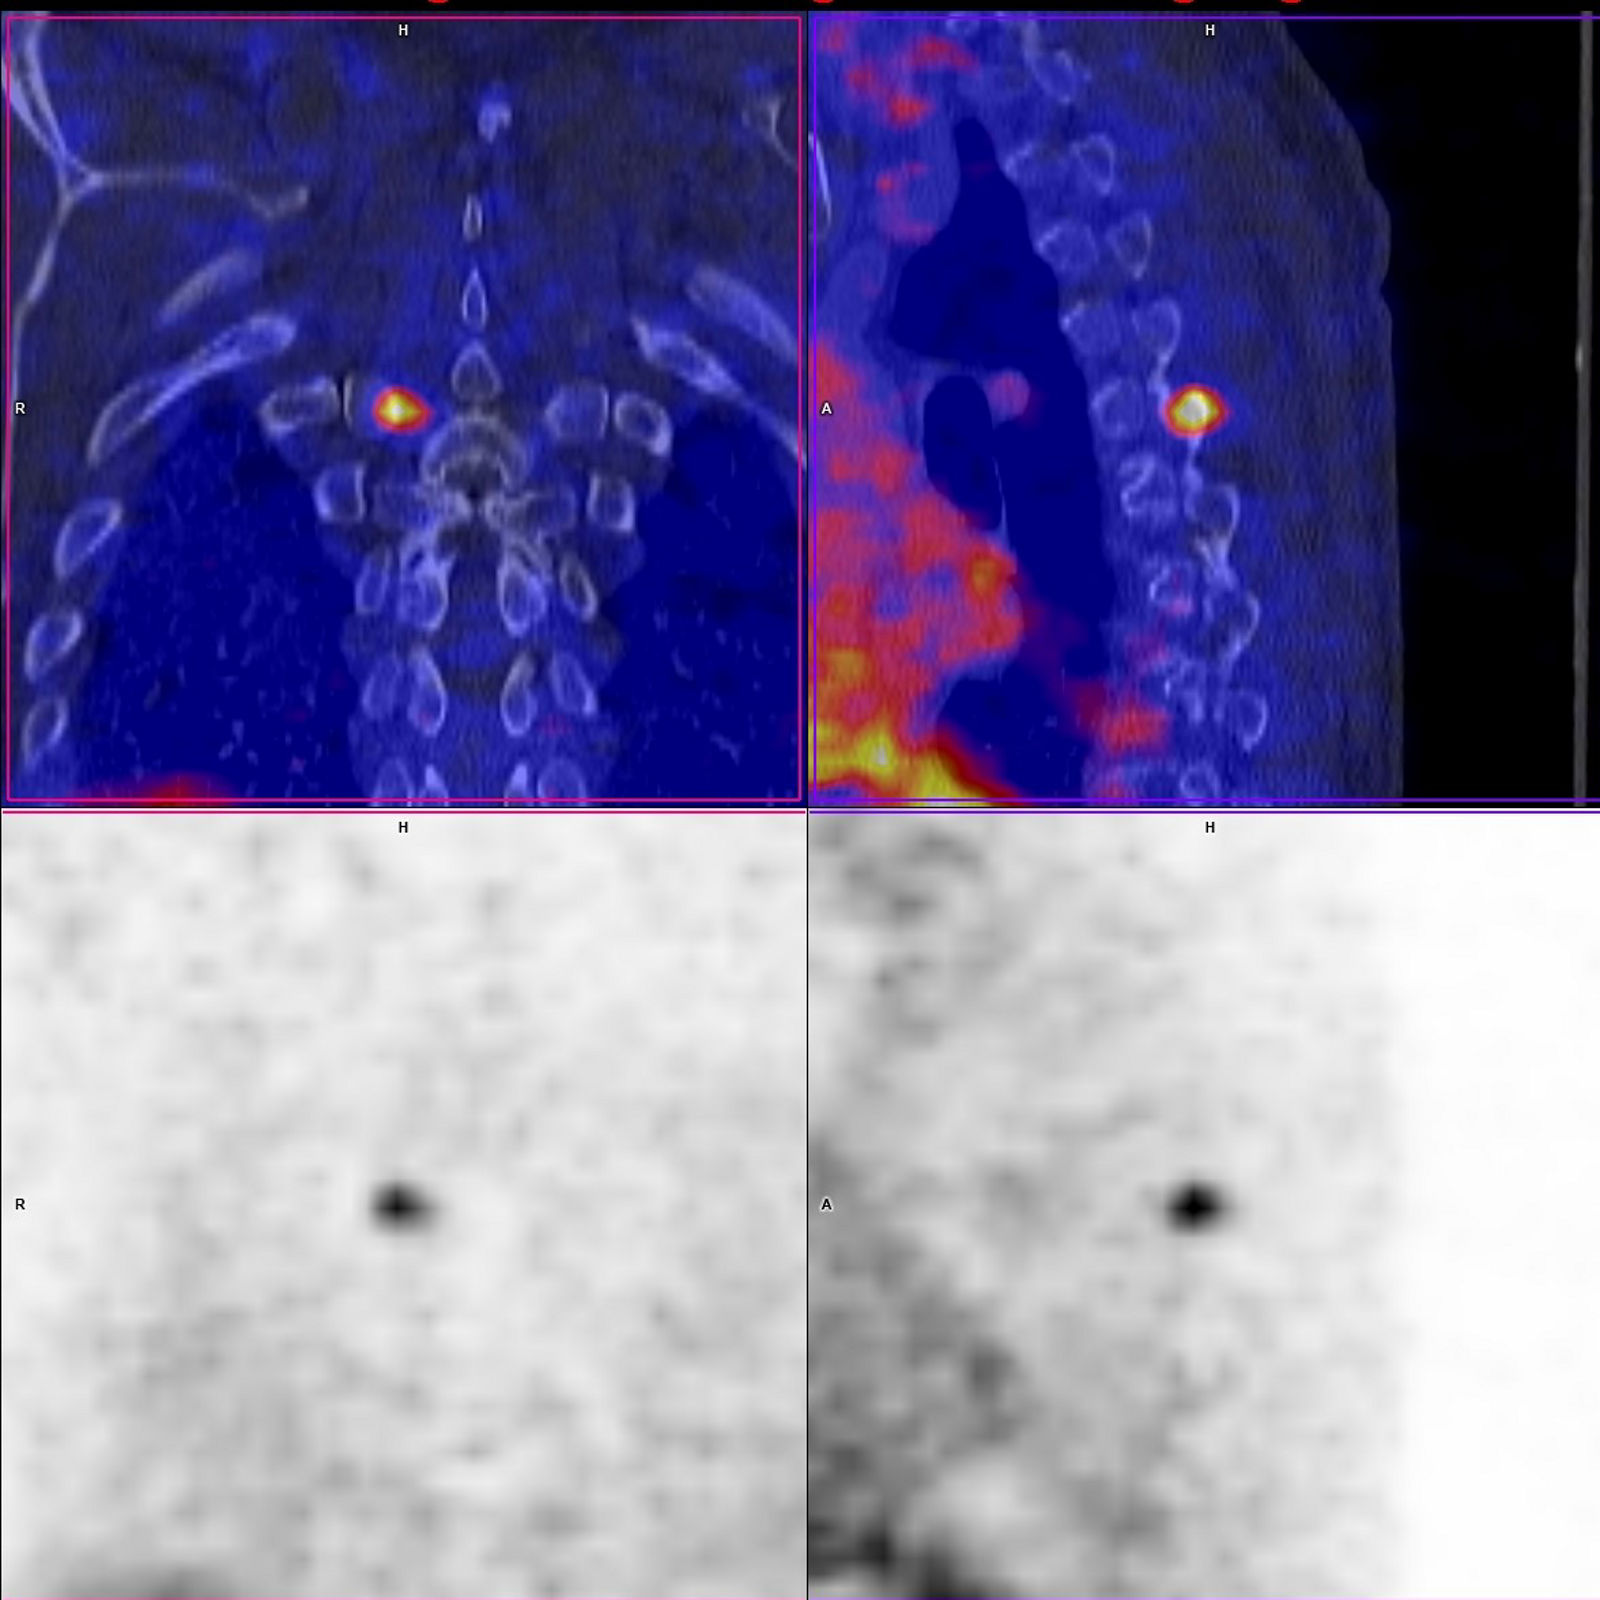

Die PET stellt durch den Einsatz schwach radioaktiver Substanzen unterschiedliche Stoffwechselvorgänge dar, die durch die Kombination mit der CT dann genau anatomisch zugeordnet werden können. Dadurch wird insbesondere in der Onkologie eine präzise und rasche Lokalisation von Tumorgewebe (Primärtumoren oder auch Metastasen) möglich und eine Therapie kann gezielter geplant werden. Manche Therapie wird durch die PET-CT in eine andere Richtung gelenkt, unnötige Therapien werden vermieden.

Der Schwerpunkt der PET-CT-Diagnostik liegt in der Onkologie. Aber auch bei neurologischen oder kardiologischen Fragenstellungen ist diese Form der Diagnostik von großer Bedeutung. Insbesondere bei der Diagnostik von Bronchialkarzinomen ist das Gerät sehr wertvoll. Seit 2010 ist die PET-CT-Untersuchung vor einem operativen Eingriff aufgrund von Lungenkrebs in den Behandlungsleitlinien festgeschrieben. Das Gerät stärkt somit die Leistungskraft des Bergischen Lungenzentrums. Um die fachübergreifende Nutzung des Gerätes zu vereinfachen und Behandlungen für den Patienten zu optimieren, sind die erzeugten Aufnahmen im gesamten System der Klinik nutzbar.